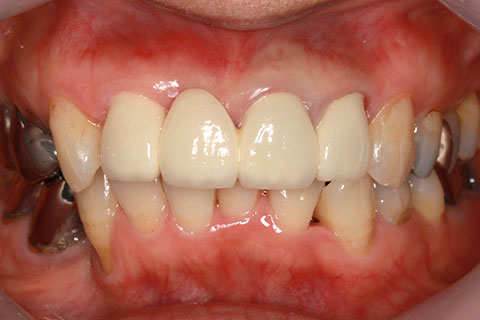

• オールセラミックの症例2

治療前

治療後

年齢・性別

45歳男性

治療期間

2ヶ月

抜歯

なし

治療費

70.4万円

備考

前歯8本の歯列不正によるセラミック治療

治療内容

歯質を削除し、セラミック冠をセメント合着

施術の副作用(リスク)

知覚過敏、歯髄炎、荷重負担